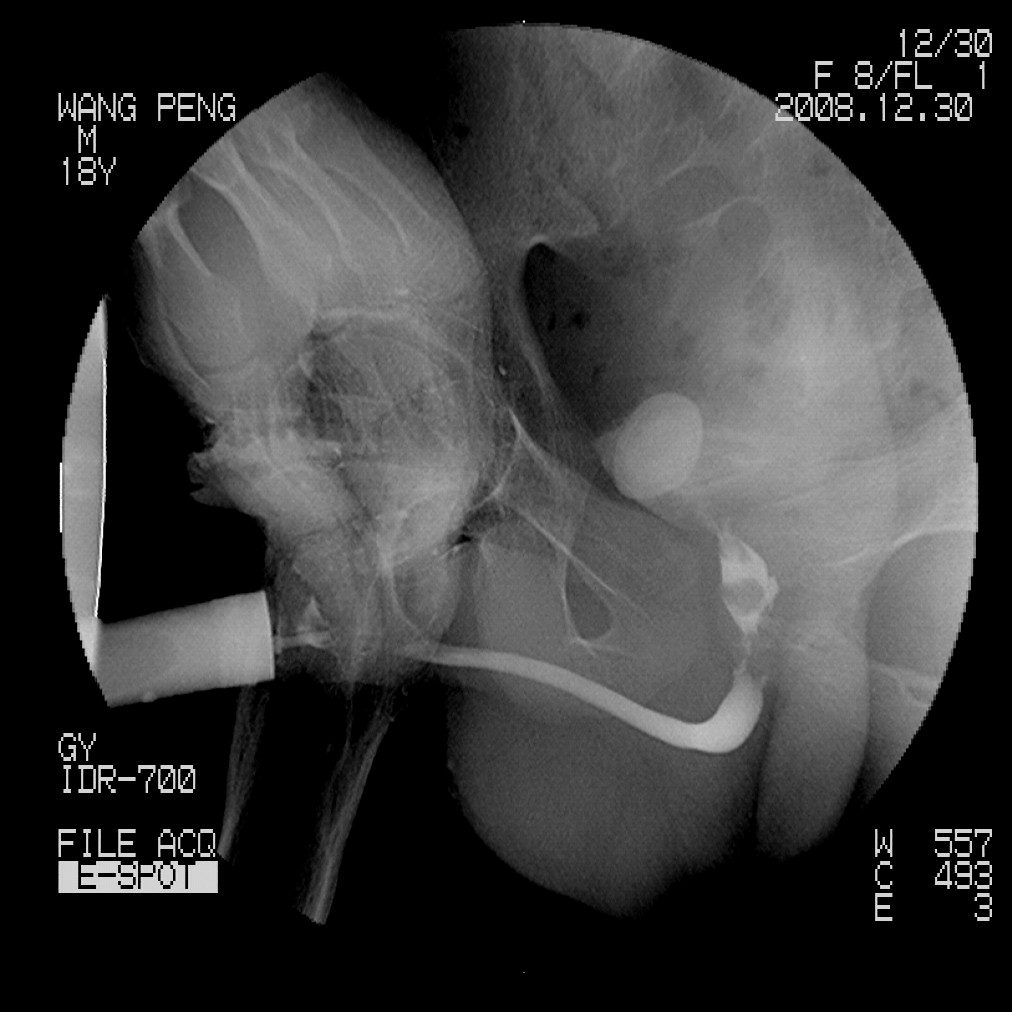

标题: X6910:经典的膀胱及尿道多发结石 [打印本页]

标题: X6910:经典的膀胱及尿道多发结石

患者,男,18岁,尿流不畅数月。

膀胱及后尿道多发结石,谢楼主分享

膀胱及尿道多发结石。

膀胱及后尿道多发结石,谢谢分享---------------------------